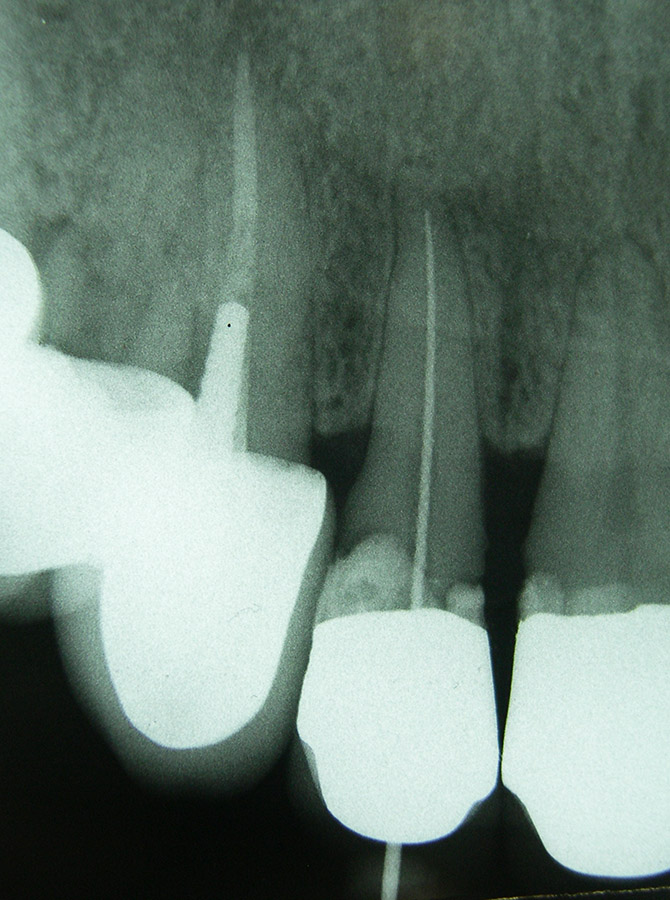

Bei einer Wurzelkanalbehandlung wird (meist unter Anästhesie) das erkrankte Nervgewebe entfernt, der Wurzelkanal mit desinfizierenden Lösungen gespült, schrittweise im Durchmesser aufbereitet, mit antibakteriellen Einlagen bis zur Schmerzfreiheit versorgt und schließlich bakteriendicht abgefüllt. Dies kann mehrere Behandlungssitzungen erfordern.

Entscheidend für den Langzeiterfolg einer Wurzelkanalbehandlung ist die exakte Füllung des gesamten Wurzelkanals bis zur Wurzelspitze. Daher verlassen wir uns hier nicht nur auf Röntgenbilder, sondern messen mit modernen Zusatzgeräten elektronisch die Länge jedes Wurzelkanals .Die Aufbereitung der Kanäle erfolgt teils von Hand, teils maschinell mit speziell dafür entwickelten, drehmomentbegrenzten Motoren und hochflexiblen Einmal-Feilen. Vor der endgültigen Wurzelfüllung wird bei uns jeder Wurzelkanal laser-sterilisiert, d.h. evtl. noch vorhandene Bakterien werden durch Zufuhr hochenergetischen Laserlichts über flexible Glasfasern abgetötet.